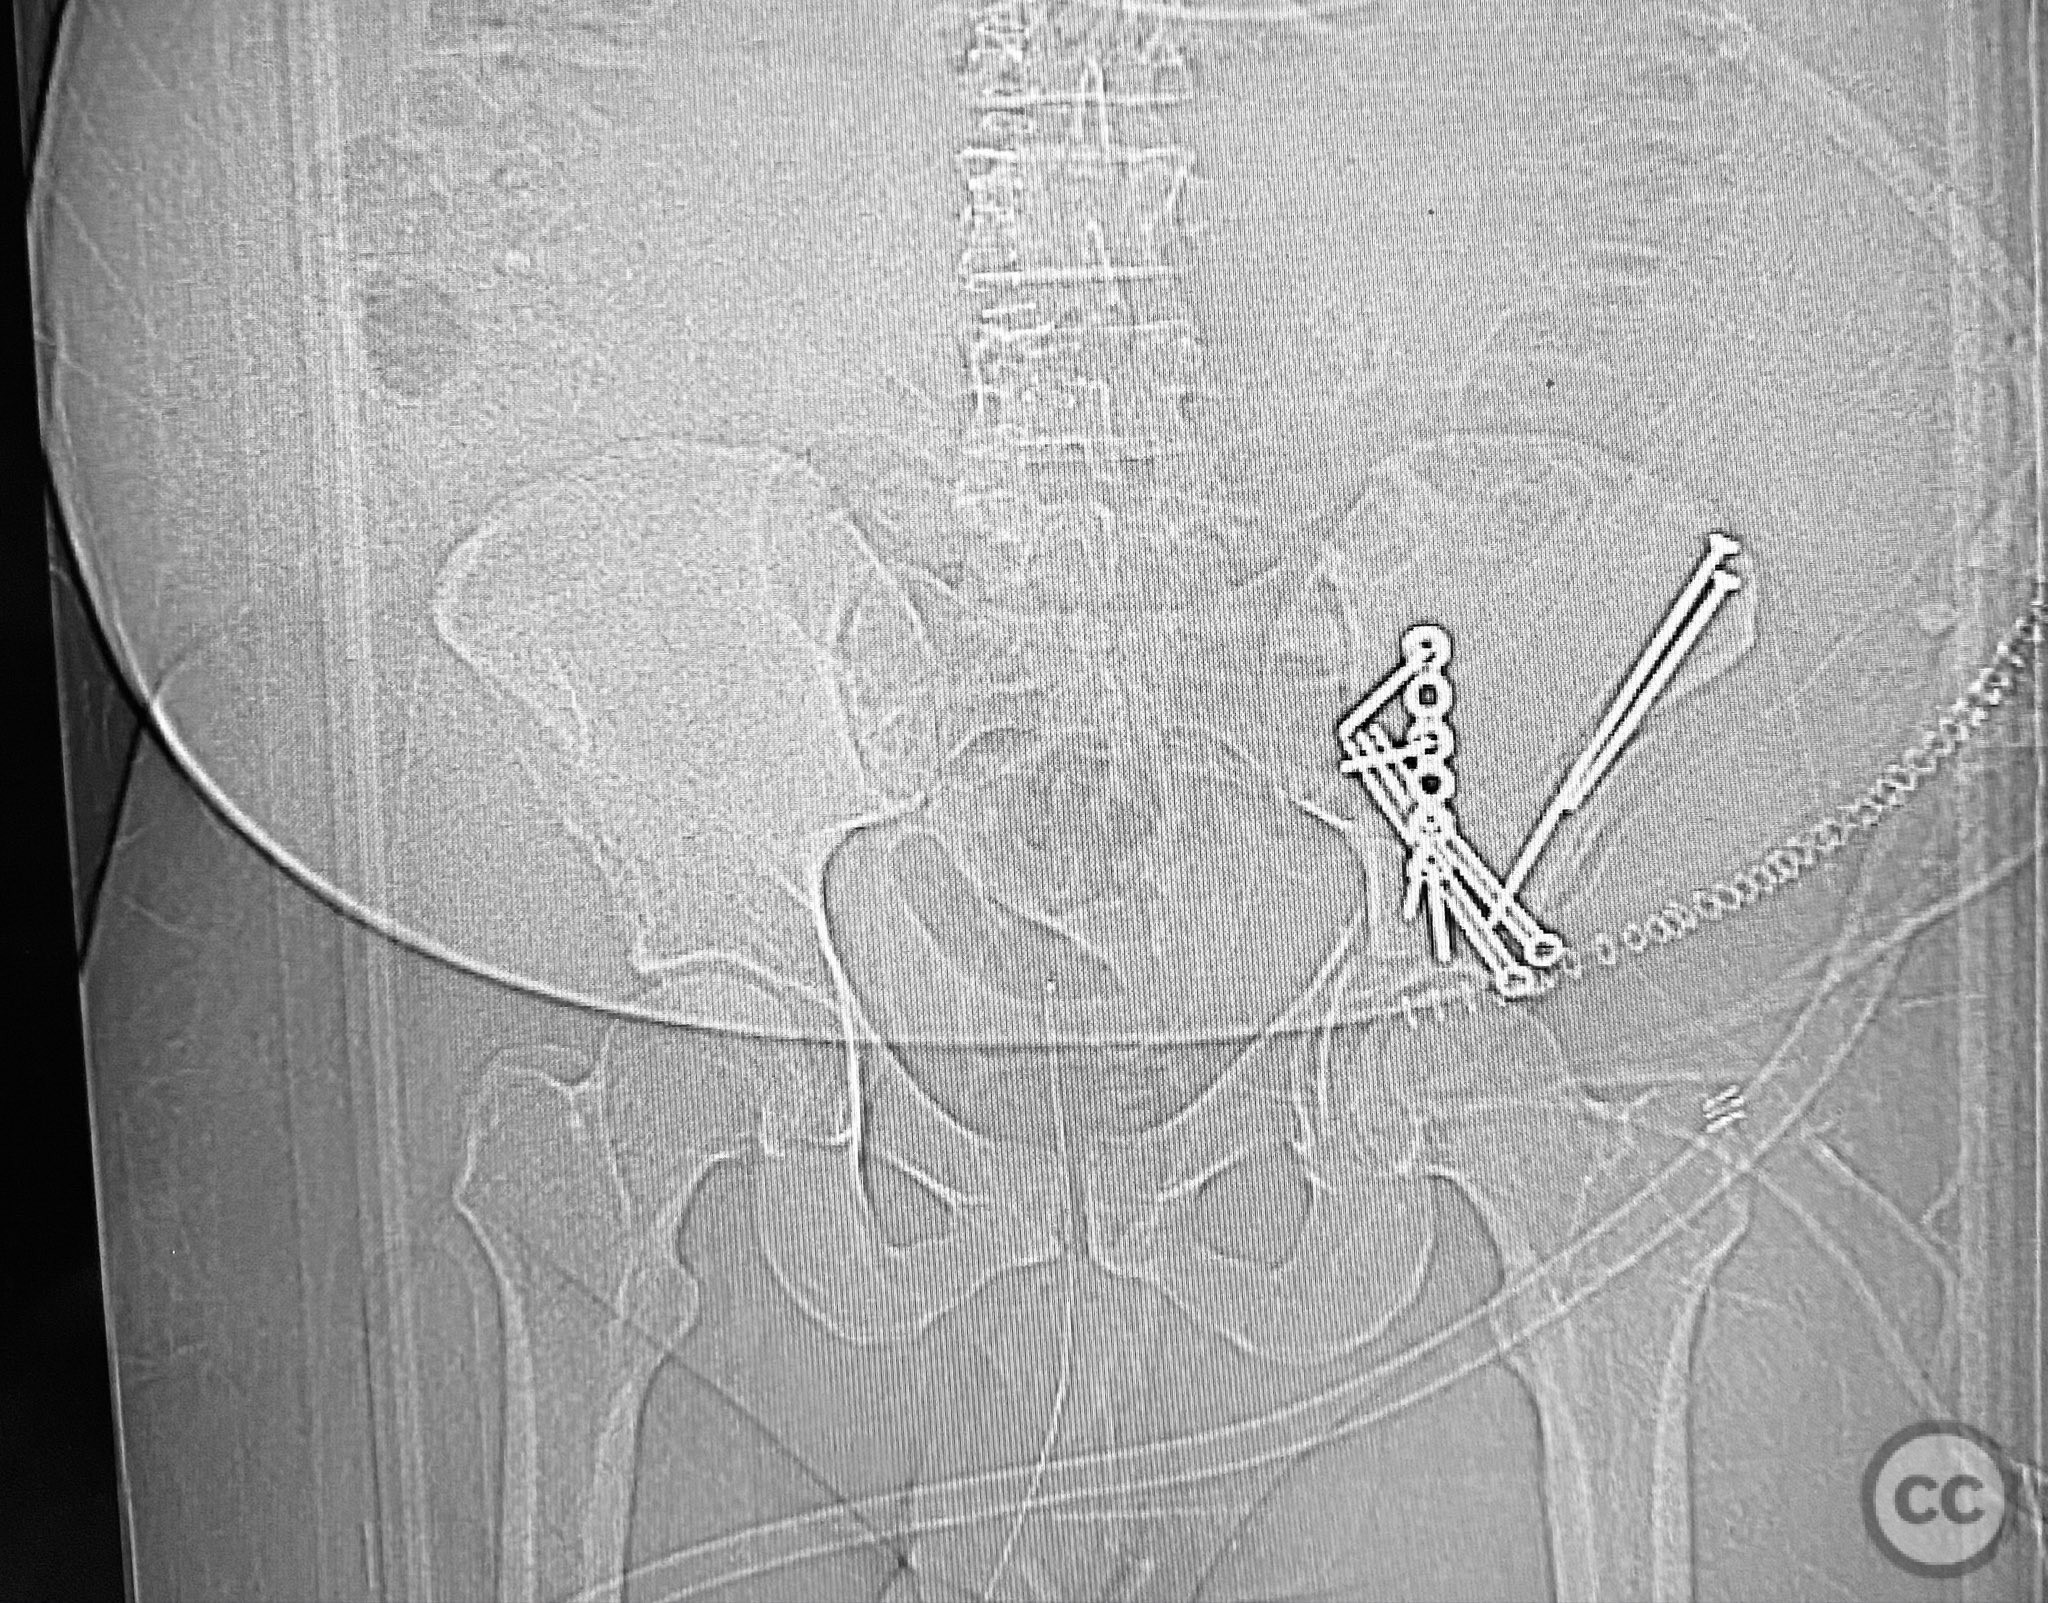

Clinical and radiological findings:  A patient presented with a displaced associated both column acetabular fracture, characterized radiographically by the presence of the "spur sign" on the anteroposterior (AP) pelvis film, indicating the caudal aspect of the intact ilium exposed by medial displacement of the articular fragments. The spur was more clearly visualized on the obturator oblique rendered image. Axial computed tomography (CT) images demonstrated the intact ilium, medially displaced anterior column (AC) and posterior column (PC) fragments, and provided detailed visualization of surrounding soft tissues, including vascular structures enhanced by contrast. Multiplanar CT reconstructions (axial, sagittal, coronal) and 3D renderings were utilized for comprehensive fracture and soft tissue assessment. The patient’s overall clinical condition was a significant factor in surgical planning.

Planning remarks:  The preoperative plan involved open reduction and internal fixation (ORIF) of the anterior column via the ilioinguinal approach, utilizing two separate windows for exposure and reduction. Given the patient’s clinical status, a staged approach was selected: initial AC reduction and fixation, with planned subsequent percutaneous reduction and fixation of the PC. Implant positioning during the first operation was planned to avoid obstructing subsequent percutaneous PC fixation.

Anatomical surgical approach:  A classical ilioinguinal approach was performed, with two windows developed: the lateral window between the musculus sartorius and musculus tensor fasciae latae, and the middle window between the musculus iliopsoas and external iliac vessels. Subcutaneous dissection was performed to create two opposing slabs of adipose tissue ("walls of fat"), minimizing random subcutaneous incisions. The anterior column fragment was exposed, reduced anatomically, and fixed under direct visualization. At a subsequent stage, percutaneous reduction and fixation of the posterior column were performed under fluoroscopic guidance, with careful trajectory planning to avoid interference from previously placed AC implants.

The operative sequence was dictated by the patient’s overall clinical status, necessitating staged management. Intraoperative attention was paid to implant placement during AC fixation to preserve access for subsequent percutaneous PC fixation. Postoperative CT confirmed satisfactory reduction and fixation of both columns, with appropriate implant positioning and no evidence of neurovascular compromise or significant soft tissue complications.